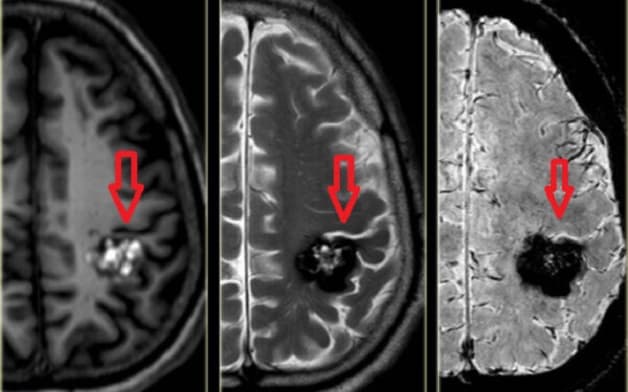

Hình ảnh khối u não được phát hiện nhờ chụp cộng hưởng từ MRI não.